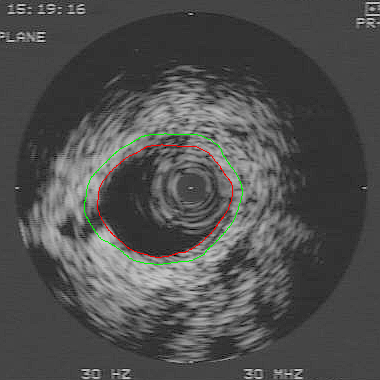

An IVUS Image with Segmented Contours of the Wall